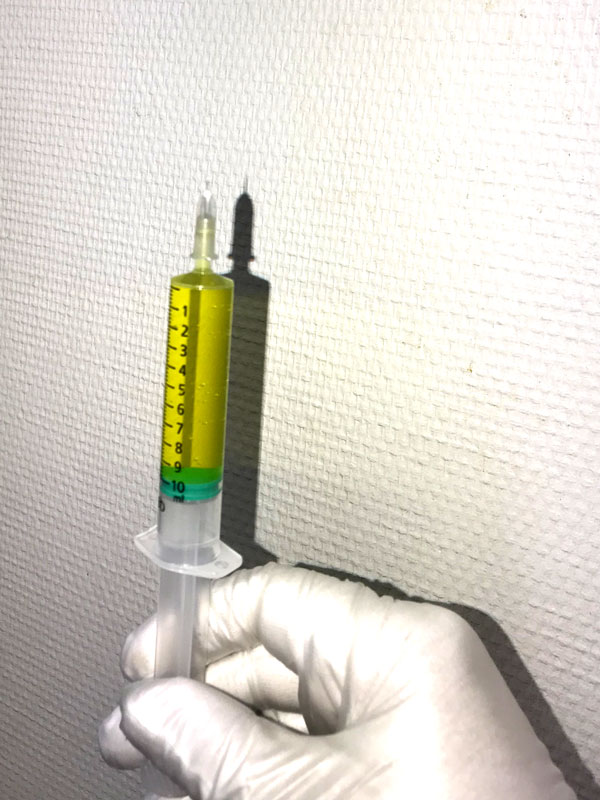

Injection sous cutanée d’une grande quantité de solutés physiologiques. Elle permet de traiter les grandes surfaces à perfuser (NACL 0,9% ou glucosé 5%)avec des médicaments :

L’hydrotomie percutanée n’injecte pas de corticoïdes retards (risques d’effets secondaires et nombre d’injections limité à 2 à 3 fois par an) ni d’acide hyaluronique dans l’articulation mais du sérum physiologique en projection orthogonale de l’articulation (NACL 0,9%) conformément à son AMM :

- Hydratation extra cellulaire

- Véhicule pour apport thérapeutique

- Rééquilibration ionique par apport de chlorure et de sodium

Le « coussin d’hydrotomie » constitue un véhicule d’apport thérapeutique selon son volume d’injection, entre les plans profonds et superficiels dans le cadre de l’AMM, du sérum physiologique (Nacl 0,9%).

En outre l’hydrotomie percutanée utilise des infiltrations locales périphériques d’anesthésiques locaux à visée antalgique (xylocaïne ou procaïne) à des doses faibles avec le Nacl 0,9% (technique tumescente utilisée en médecine esthétique) : création du coussin d’hydrotomie ciblé sur la lésion. Cette technique est utilisée par tous les praticiens, depuis plusieurs décennies, notamment en médecine générale pour effectuer des petits actes médico-chirurgicaux (points de suture ou ablation de petites lésions…).

Avec l’injection des solutions salines physiologiques en grande quantité, l’hydrotomie percutanée va pouvoir rétablir un équilibre « iso-osmotique » régularisant ainsi l’osmolalité et « l’hypertonie inflammatoire ». Disons plus simplement que « l’eau éteint le feu » avec l’effet des grandes dilutions.